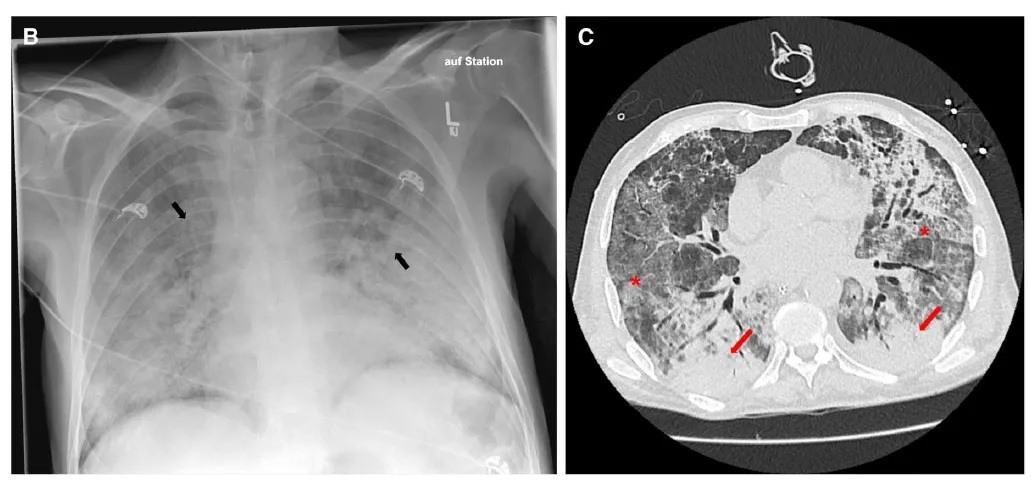

* A radiografia de tórax mostrou infiltrados no pulmão esquerdo e a tomografia computadorizada revelou consolidações extensas com opacidades em vidro fosco nos lobos inferiores de ambos os pulmões.